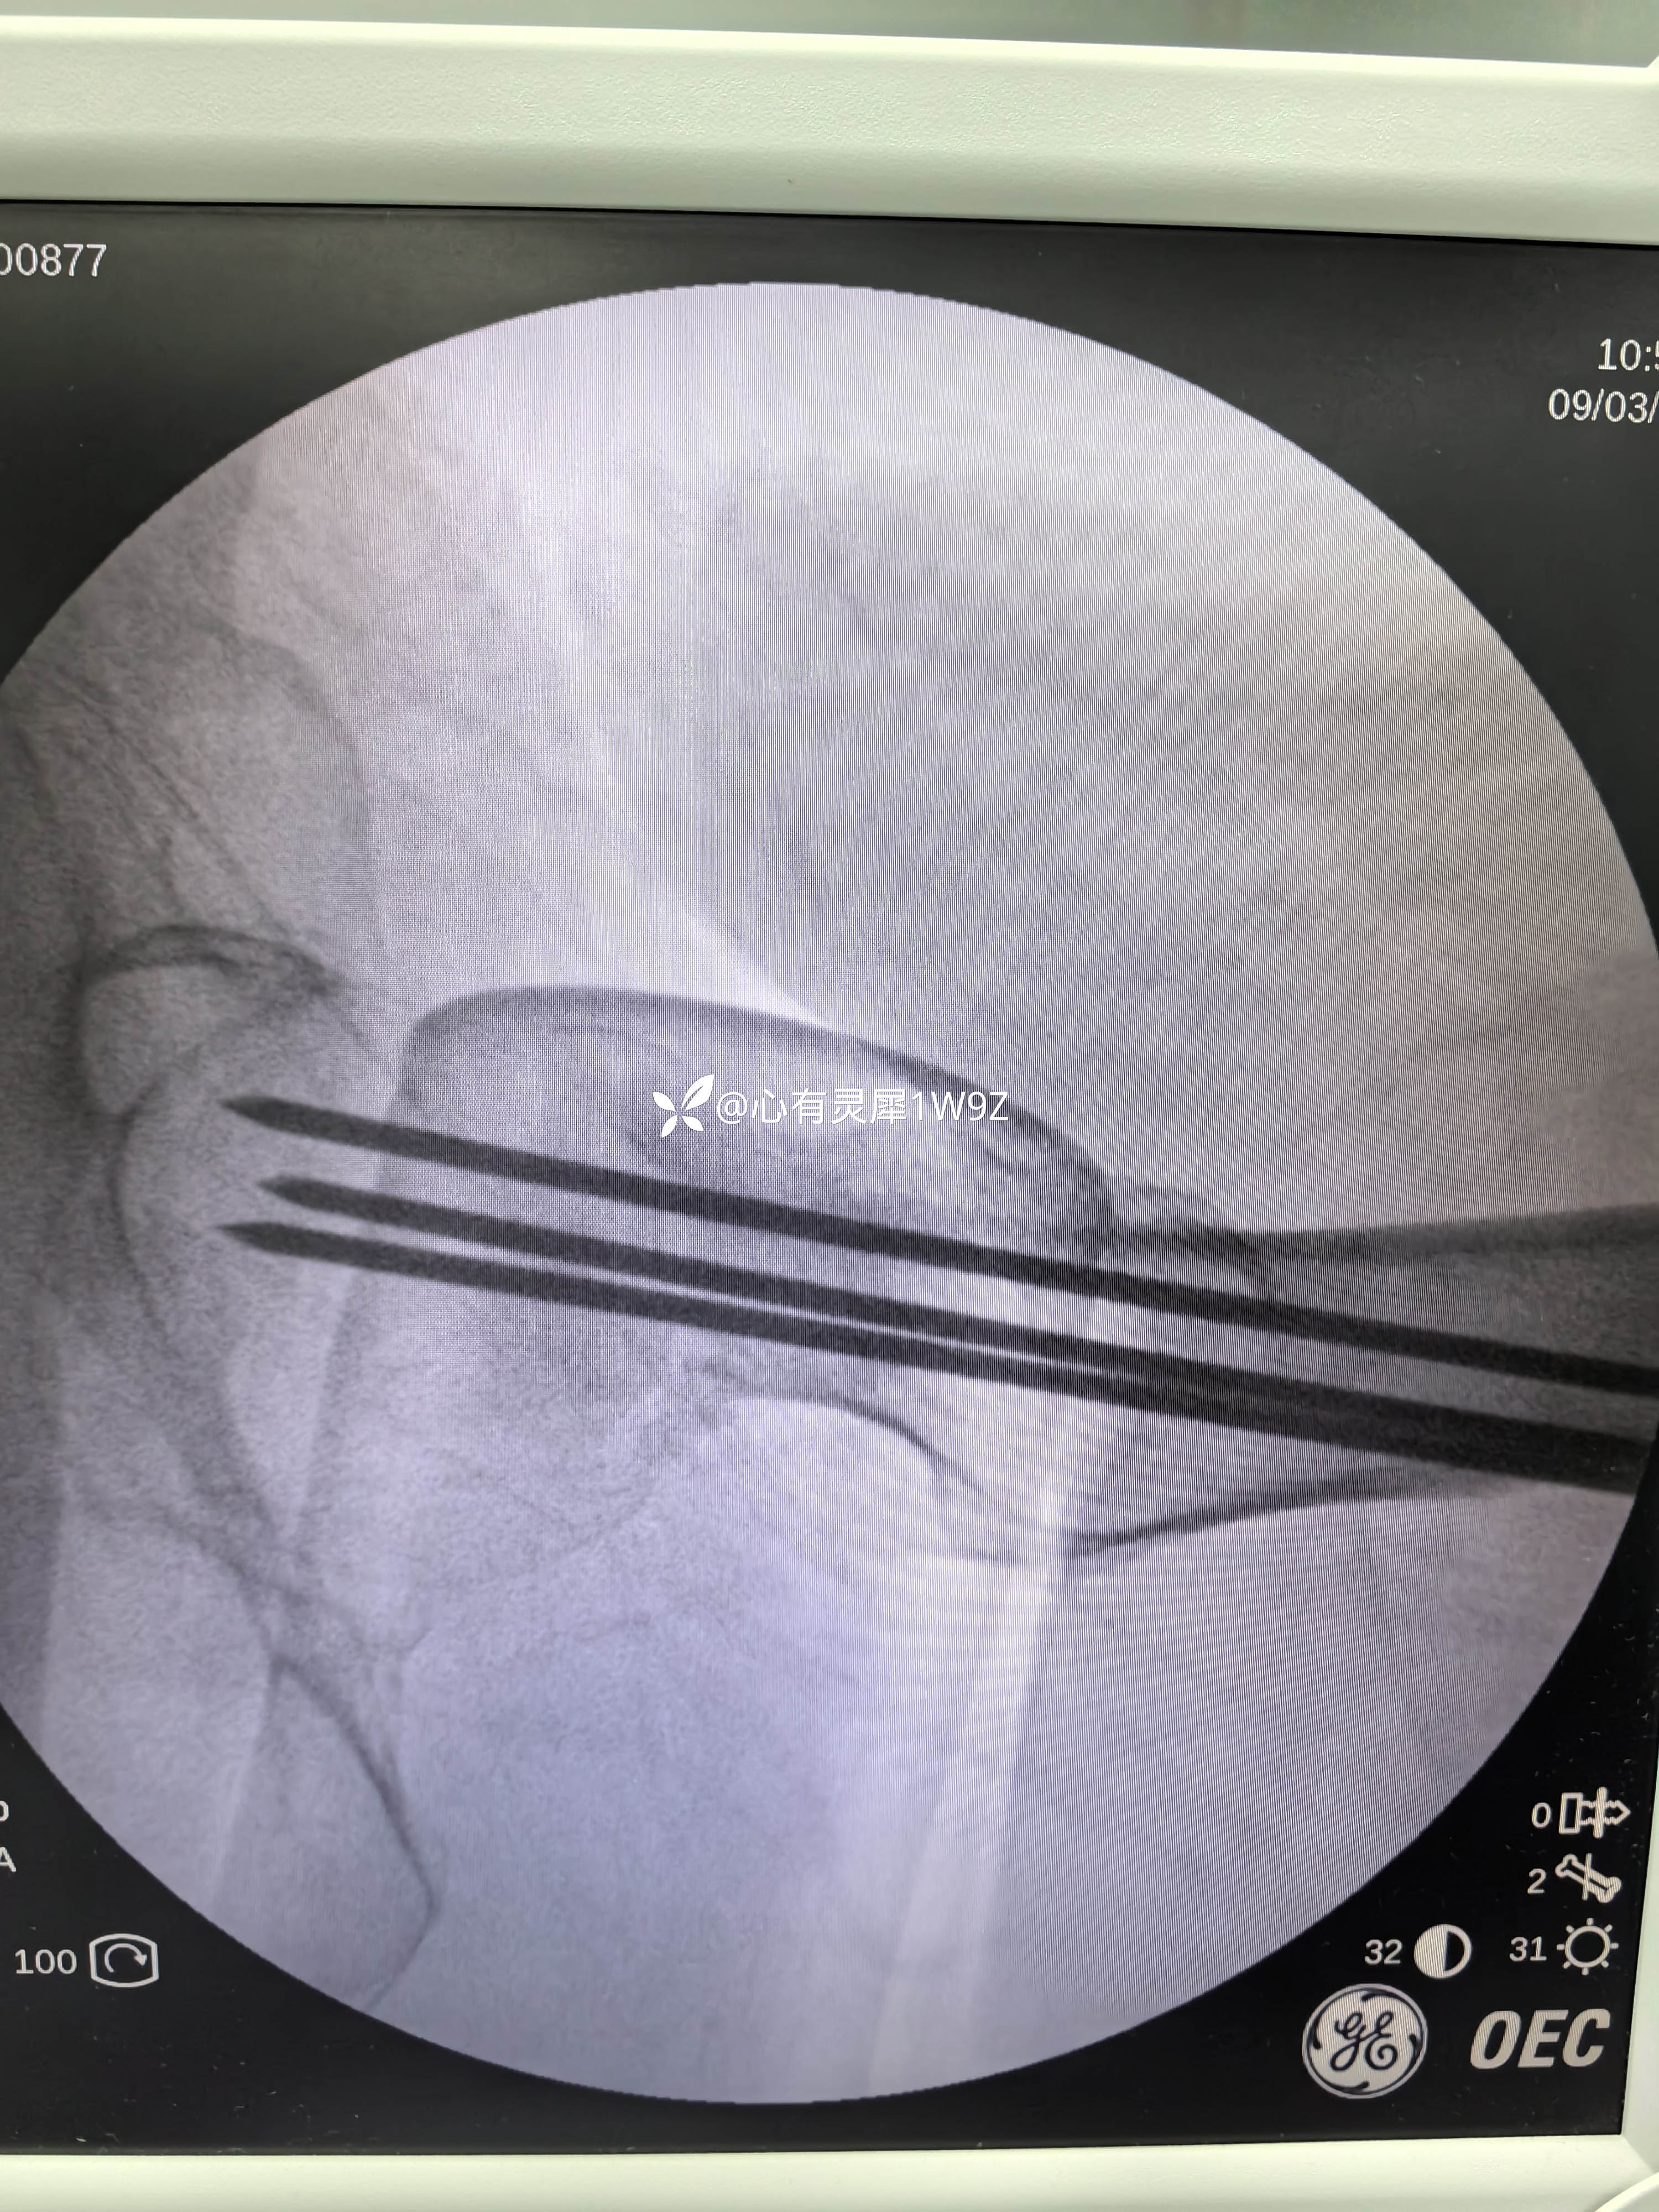

向患者及家属讲解治疗方案。患者和家属选择做内固定。积极准备后在24小时内手术。椎管麻醉,手术顺利,计划首先闭合复位,复位失败就切开复位,三枚加压空心钉固定。

2,关于贴壁,平行,长度,角度。自己感觉这次平行和长度都比较满意,贴壁还可以,角度不是很完美,感觉可以接受,就没有再调整。